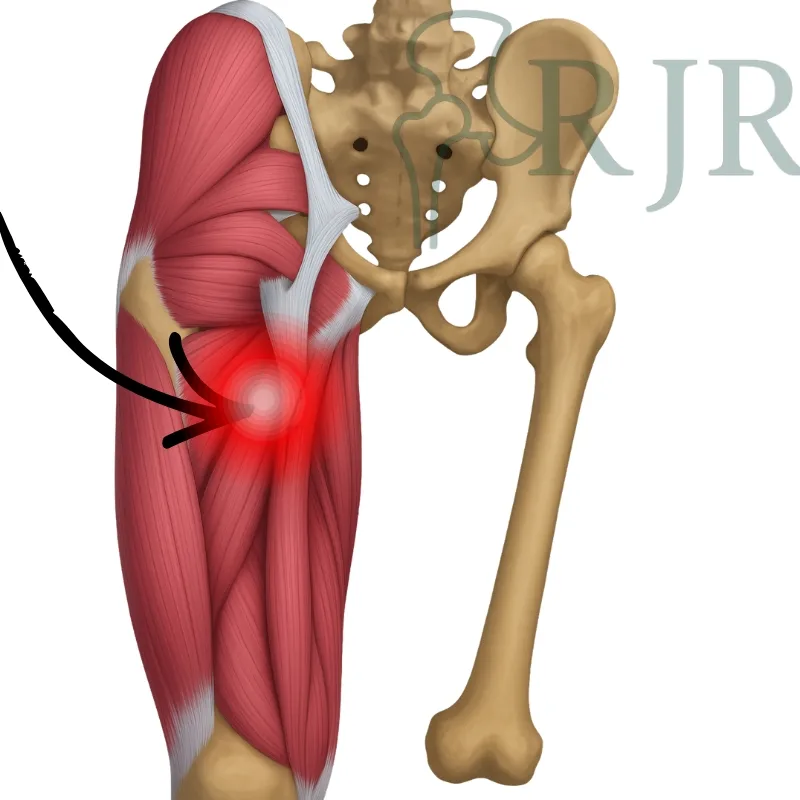

Lesões posteriores da coxa

Comuns em esportes como futebol e corrida. Uma avaliação cuidadosa guia um plano de reabilitação eficaz.

Bursite trocantérica

A tendinite glútea e bursite são causas comuns de dor lateral. Com tratamento adequado, retomamos sua rotina com conforto.